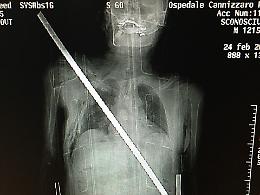

«Io, trafitto da una barra di ferro salvato dagli "angeli" del Cannizzaro»